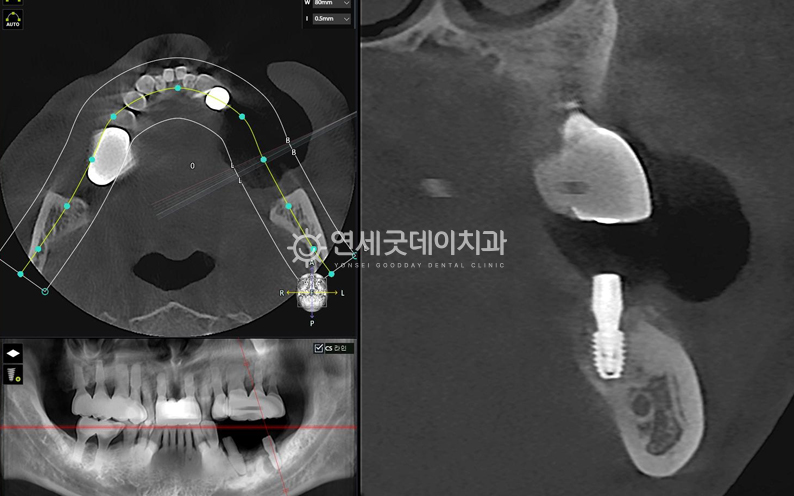

엑스레이를 보면 #35 부위에 치근단 병소가 확인되었고,

치근단염이 관찰되었던 #35 부위를 발치 및 제거 후에는 추후 새로운 임플란트를 안전하게 심고,

치료전과 후를 보시면 완전히 내려 앉았던 잇몸뼈가